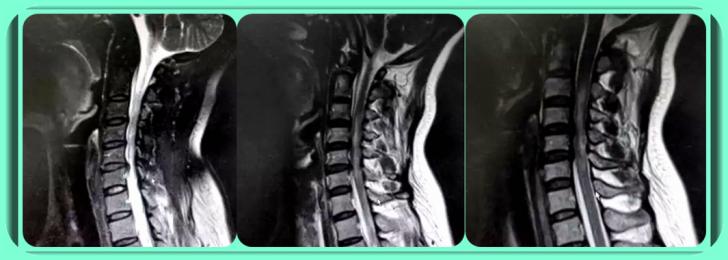

晏怡教授:颈椎管狭窄的诊断除了要结合患者病史、体征、症状等外,多数时候还需要借助CT、脊髓造影、磁共振及X线片检查等影像学检查,不同影像学检查有着不同作用。比如,磁共振能够发现颈椎椎管前后径变窄、脊髓受压等。